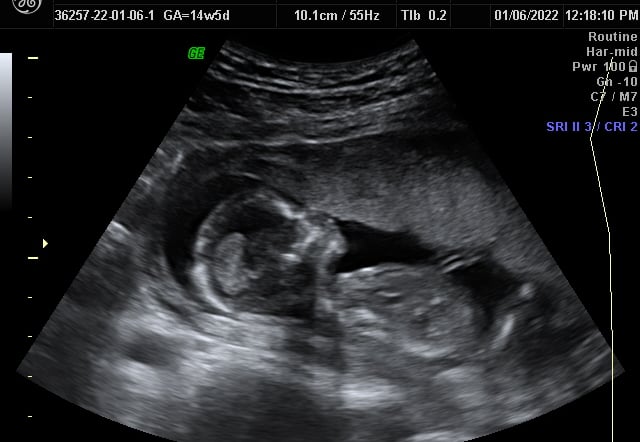

Our Gallery

Explore beautiful moments captured during our 3D and 4D sessions.